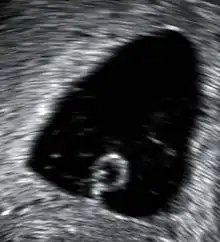

An ultrasound showing a gestational sac containing a yolk sac but no embryo

An anembryonic pregnancy (also called an "empty sac" or "blighted ovum") is a condition where the gestational sac develops normally, while the embryonic part of the pregnancy is either absent or stops growing very early. This accounts for approximately half of miscarriages. All other miscarriages are classified as embryonic miscarriages, meaning that there is an embryo present in the gestational sac. Half of embryonic miscarriages have aneuploidy (an abnormal number of chromosomes).[50]